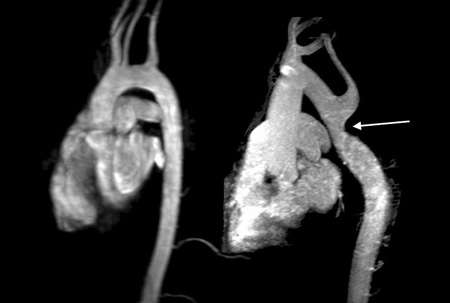

Cardiac MRI revealing normal aortic arch in ‘candy cane’ configuration on the left, compared with a previously undiagnosed aortic coarctation, just after the origin of the left subclavian artery (arrow), detected by MRI in an adult woman with Turner syndrome with severe upper body hypertension

From the personal collection of Carolyn Bondy, MS, MD (NIH study)